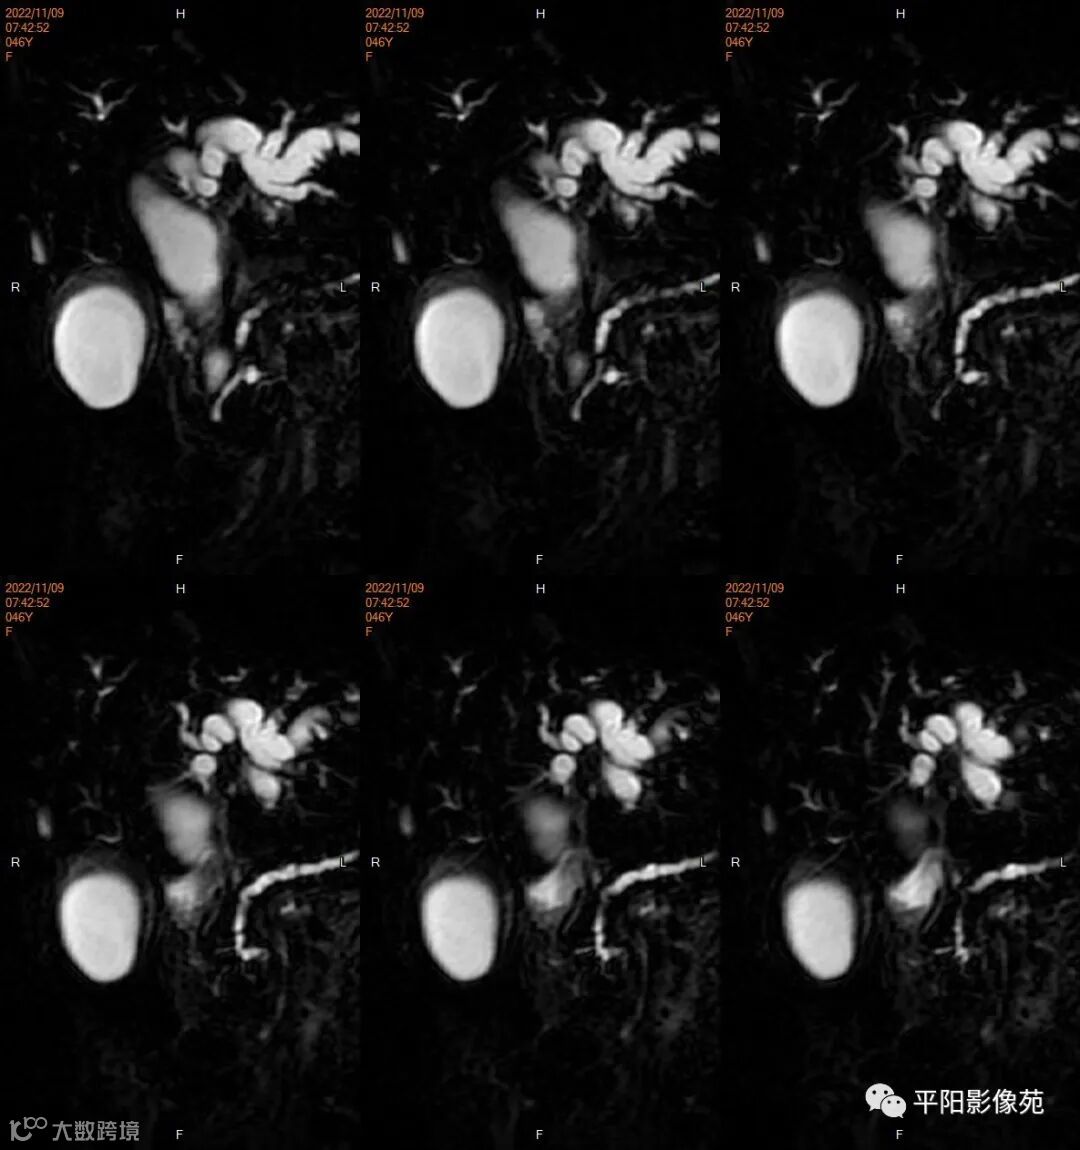

影像学检查

MR

影像表现: